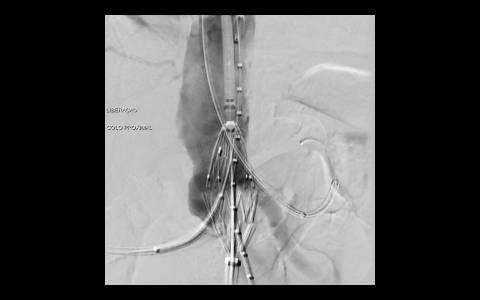

A avaliação por tomografia computadorizada evidenciou um aneurisma infra-renal de colo hostil e acessos vasculares com muita ateromatose. Diante do contexto clínico e de imagem foi optado pelo tratamento endovascular com endoprótese de baixo perfil Incraft CORDIS e técnica de Snorkel Grafts com stents Palmaz CORDIS para as artérias renais.